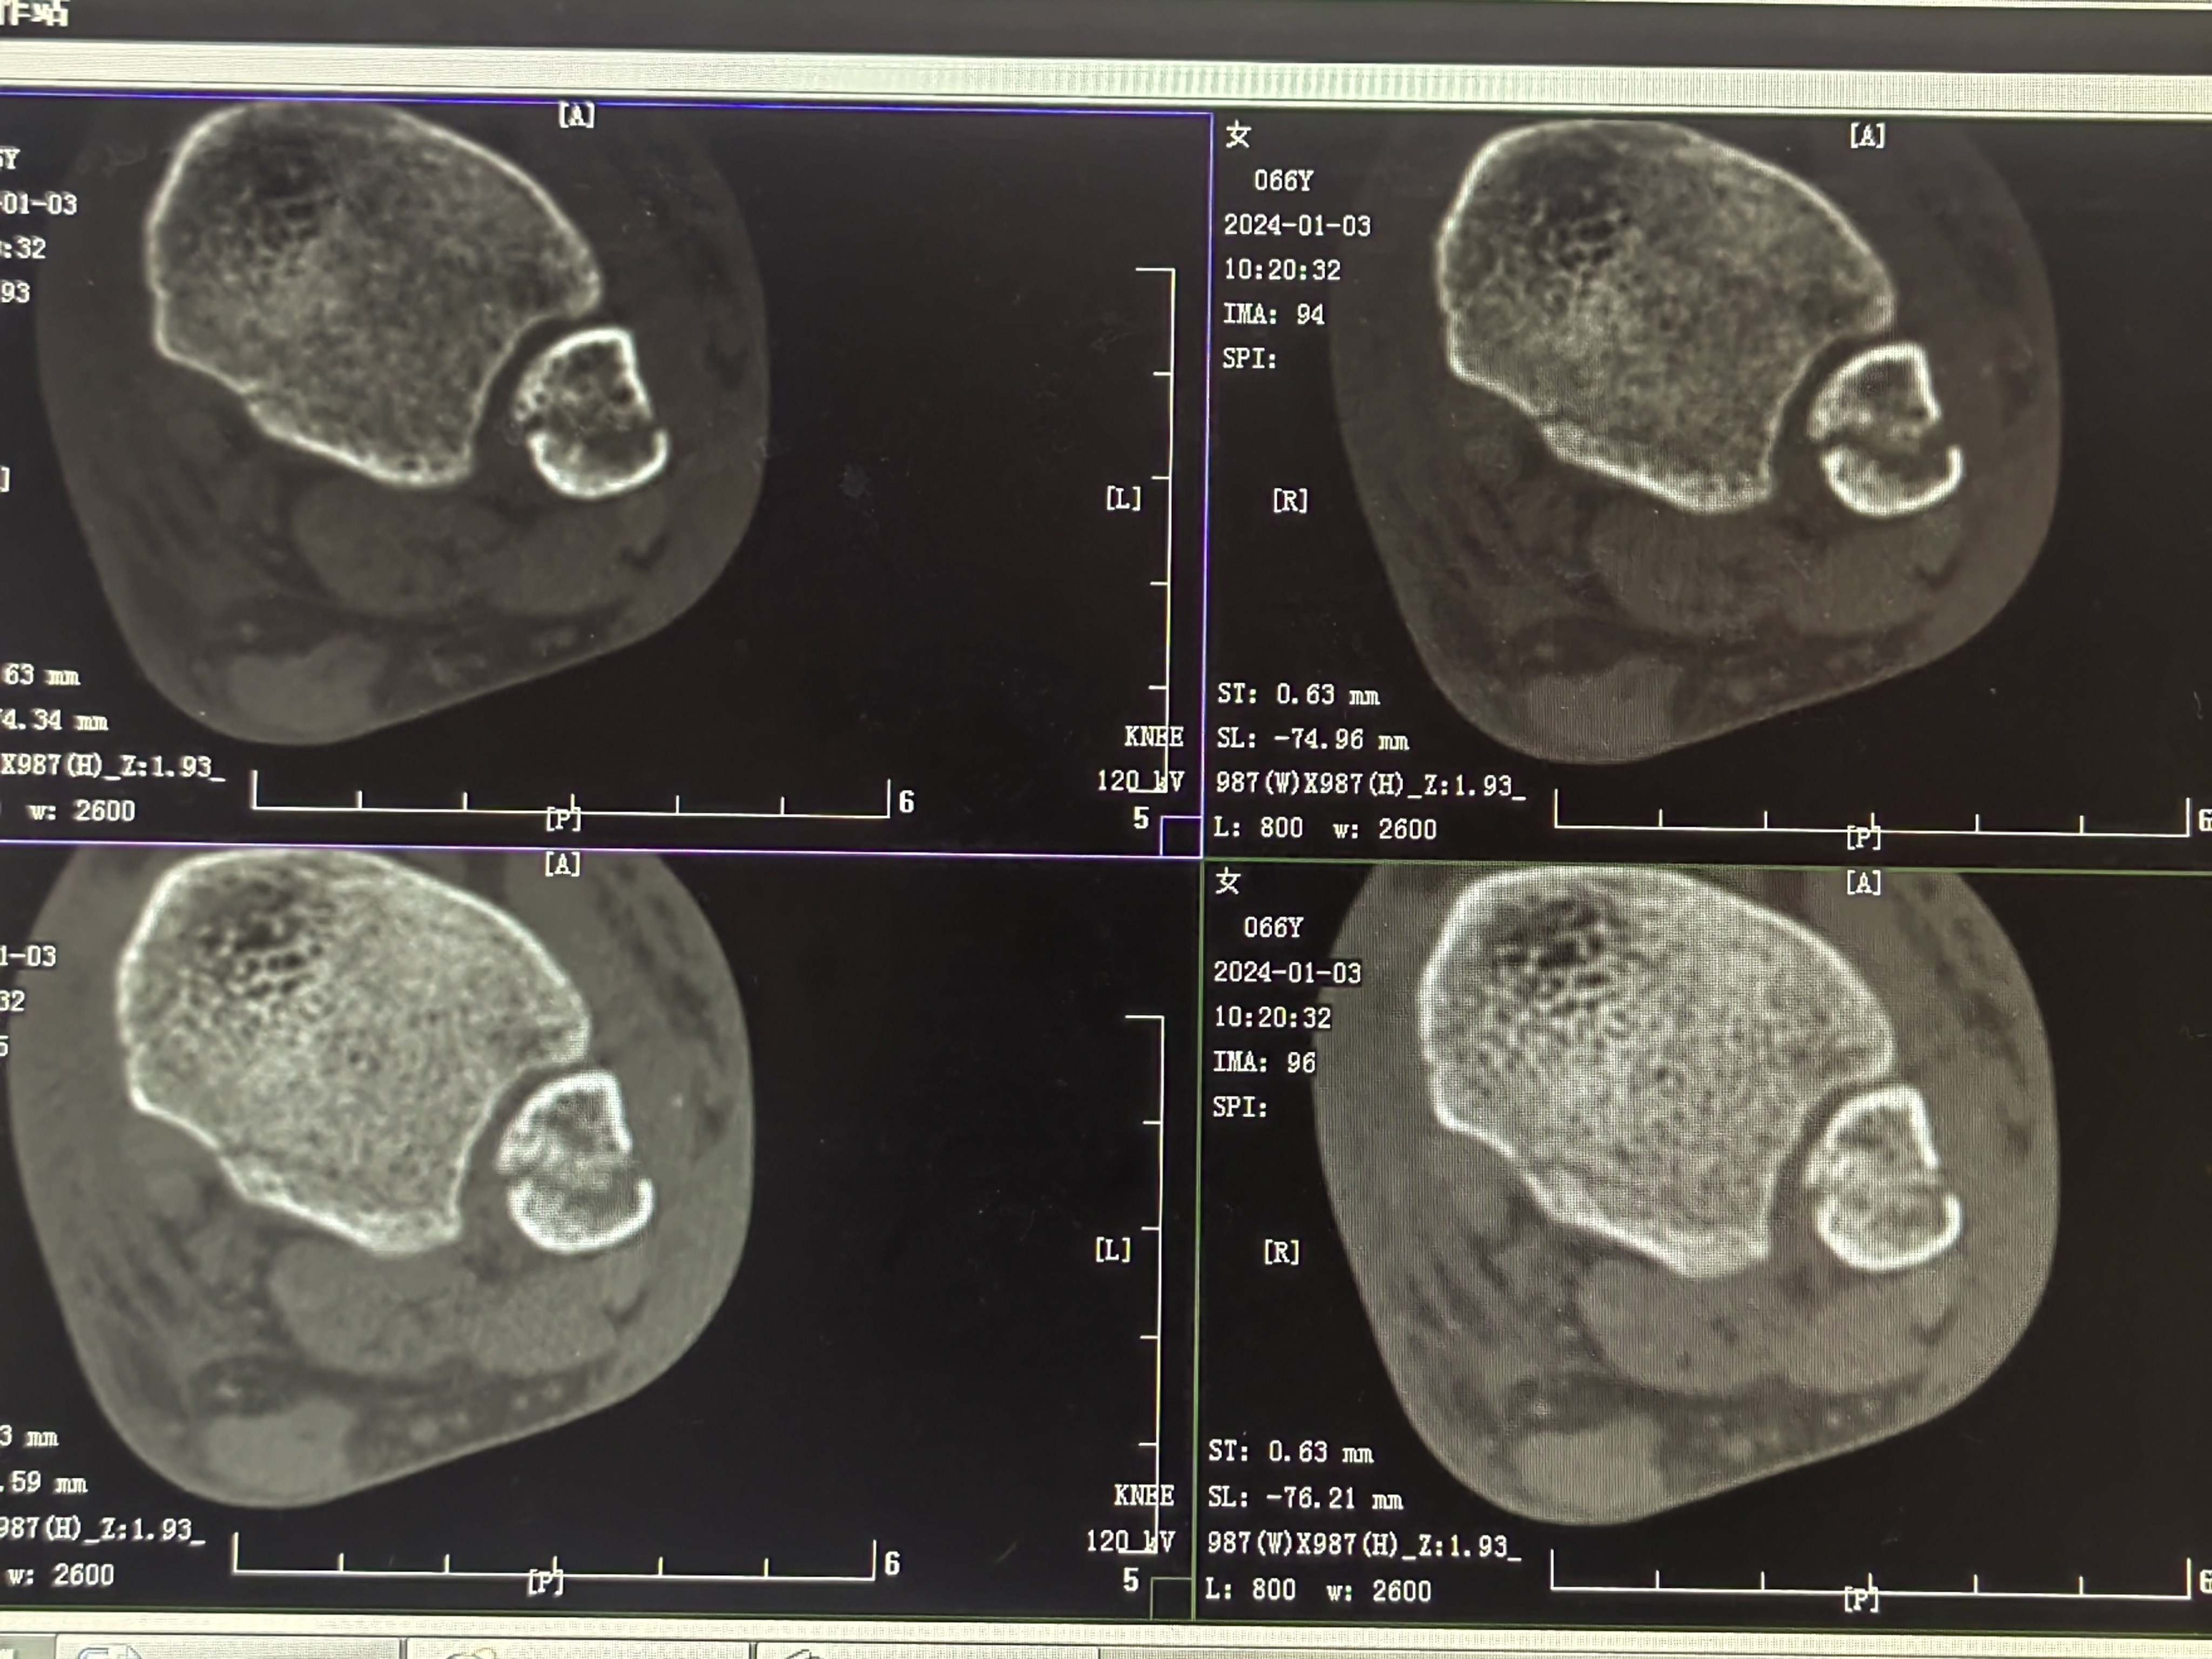

患者矫,女,66岁,左踝扭伤肿痛畸形2小时

初步诊断:左踝关节骨折(L-H分型:旋后外旋型IV)

CT